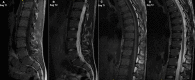

Methods: All climbers of the Swedish national sport climbing team (n = 8), and individuals having trained for selection to the national team (n = 11), were prospectively included. A control group, matched in age and sex, were recruited. All participants underwent a thoracolumbar MRI (1.5 T, T1- and T2-weighted imaging), evaluated according to Pfirrmann classification, modified Endplate defect score, Modic changes, apophyseal injuries and spondylolisthesis. Pfirrmann ≥ 3, Endplate defect score ≥ 2 and Modic ≥ 1 was defined as degenerative findings.

Results: Fifteen individuals, 8 women, participated in both the climbing group (mean age 23.1, SD 3.2 years) and the control group respectively (mean age 24.3, SD 1.5 years). In the climbing group, 6.1% of the thoracic and 10.6% of the lumbar intervertebral discs showed signs of degeneration according to Pfirrmann. One disc with a grade above 3 was present. Modic changes in the thoracic/lumbar spine were prevalent in 1.7%/1.3% of the vertebrae. Degenerative endplate changes according to the Endplate defect score were found in 8.9% and 6.6% of the thoracic and lumbar spinal segments of the climbing group, respectively. Two apophyseal injuries were found, while no participants displayed signs of spondylolisthesis. There was no difference in point-prevalence of radiographic spinal changes between climbers and controls (0.07 < p < 1.0).